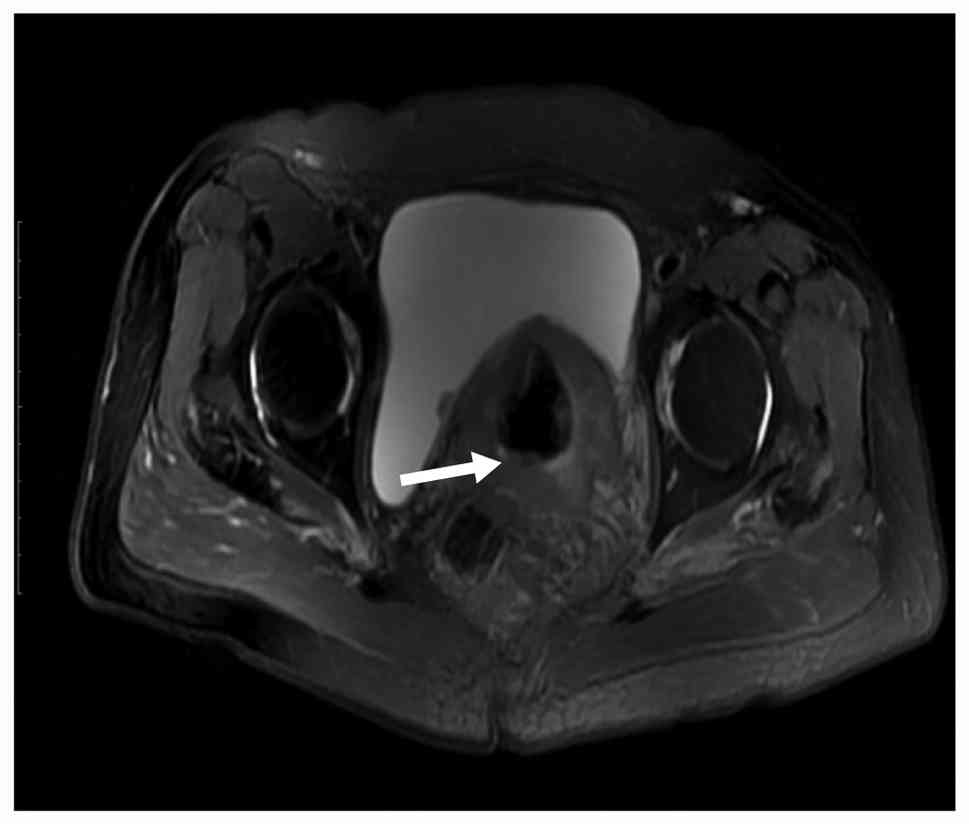

MRI diagnostic image examples

Diffusion-weighted imaging axial

sequence showing multiple lymph node metastases (white arrow) in

the pelvic region.

Figure 2.

Diffusion-weighted imaging axial sequence showing multiple lymph node metastases (white arrow) in the pelvic region.